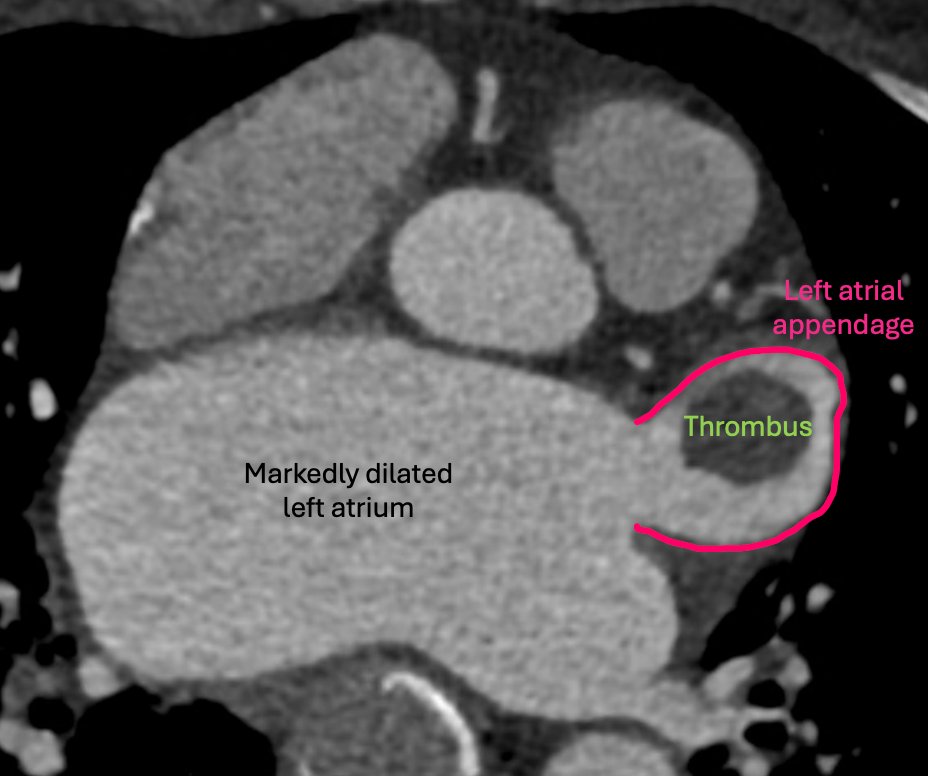

🫀 Answer: left atrial appendage thrombus 🩸 🗝️Key clues on cardiac CTA: • Persistent filling defect on delayed imaging • Sharp margins (not wispy stasis) • High-risk setup in atrial fibrillation 🚨 Not just a cool image—this finding changes management now. Anticoagulate

🫀 Heart CTA case 🫀 🧑‍🦱Patient with atrial fibrillation undergoing workup for Watchman placement—take a close look at the left atrial appendage 👀 💊What finding requires immediate management? Drop your answer below ⬇️ #RadTwitter #CardiacImaging #Radiology #Cardiology